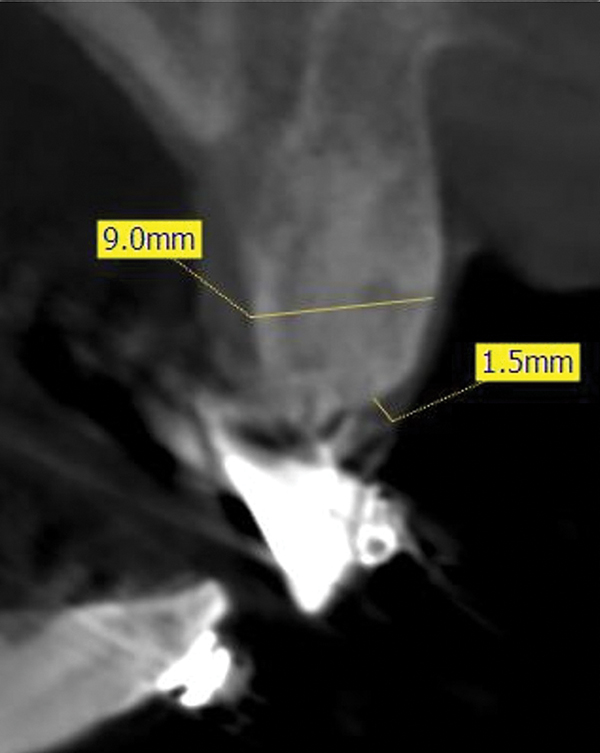

Double Track Sign In Pyloric Stenosis - Jul 22, 2021 · pyloric stenosis, also known as infantile hypertrophic pyloric stenosis (ihps), is an uncommon condition in infants characterized by abnormal thickening of the pylorus muscles in the stomach leading to gastric outlet obstruction.

Clinically infants are well at birth. Fig 9 Hypertrophic Pyloric Stenosis In A 2 Week Old Patient A B Transverse A And Longitudinal B Views Show Concentric Hypertrophy Of The Muscular Layer Of The Pyloric Canal Arrows Note The Double Track Sign Arrowheads And Distended Stomach